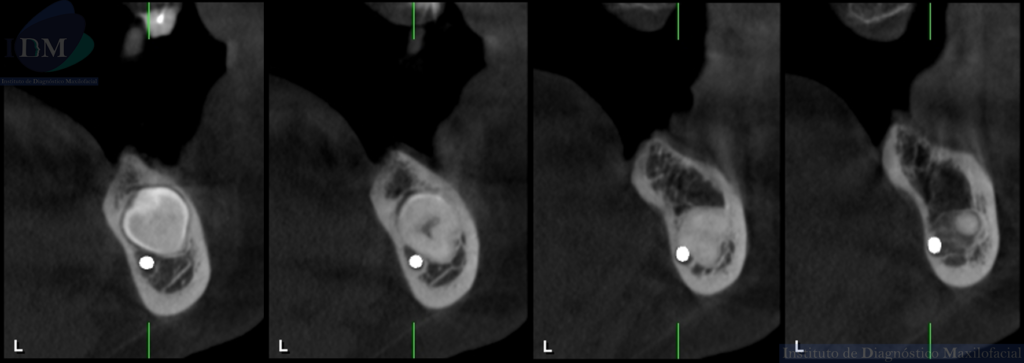

CORTES TRANSAXIALES

A la evaluación de la radiografía panorámica se evidencia reabsorción ósea alveolar bimaxilar, edéntulo parcial bimaxilar y presencia de múltiples implantes con prótesis sobre implantes así como tratamientos restaurativos. Siendo lo más destacado una molar retenida en cuerpo mandibular izquierdo, la cual esta mesioangulada.

Siendo así que en la tomografía volumétrica de haz cónico se evidencia una hipercementosis radicular, con los segmentos radiculares contactando con el conducto dentario inferior. Finalmente se evidencia un borramiento del espacio del ligamento periodontal compatible con anquilosis dentaria.